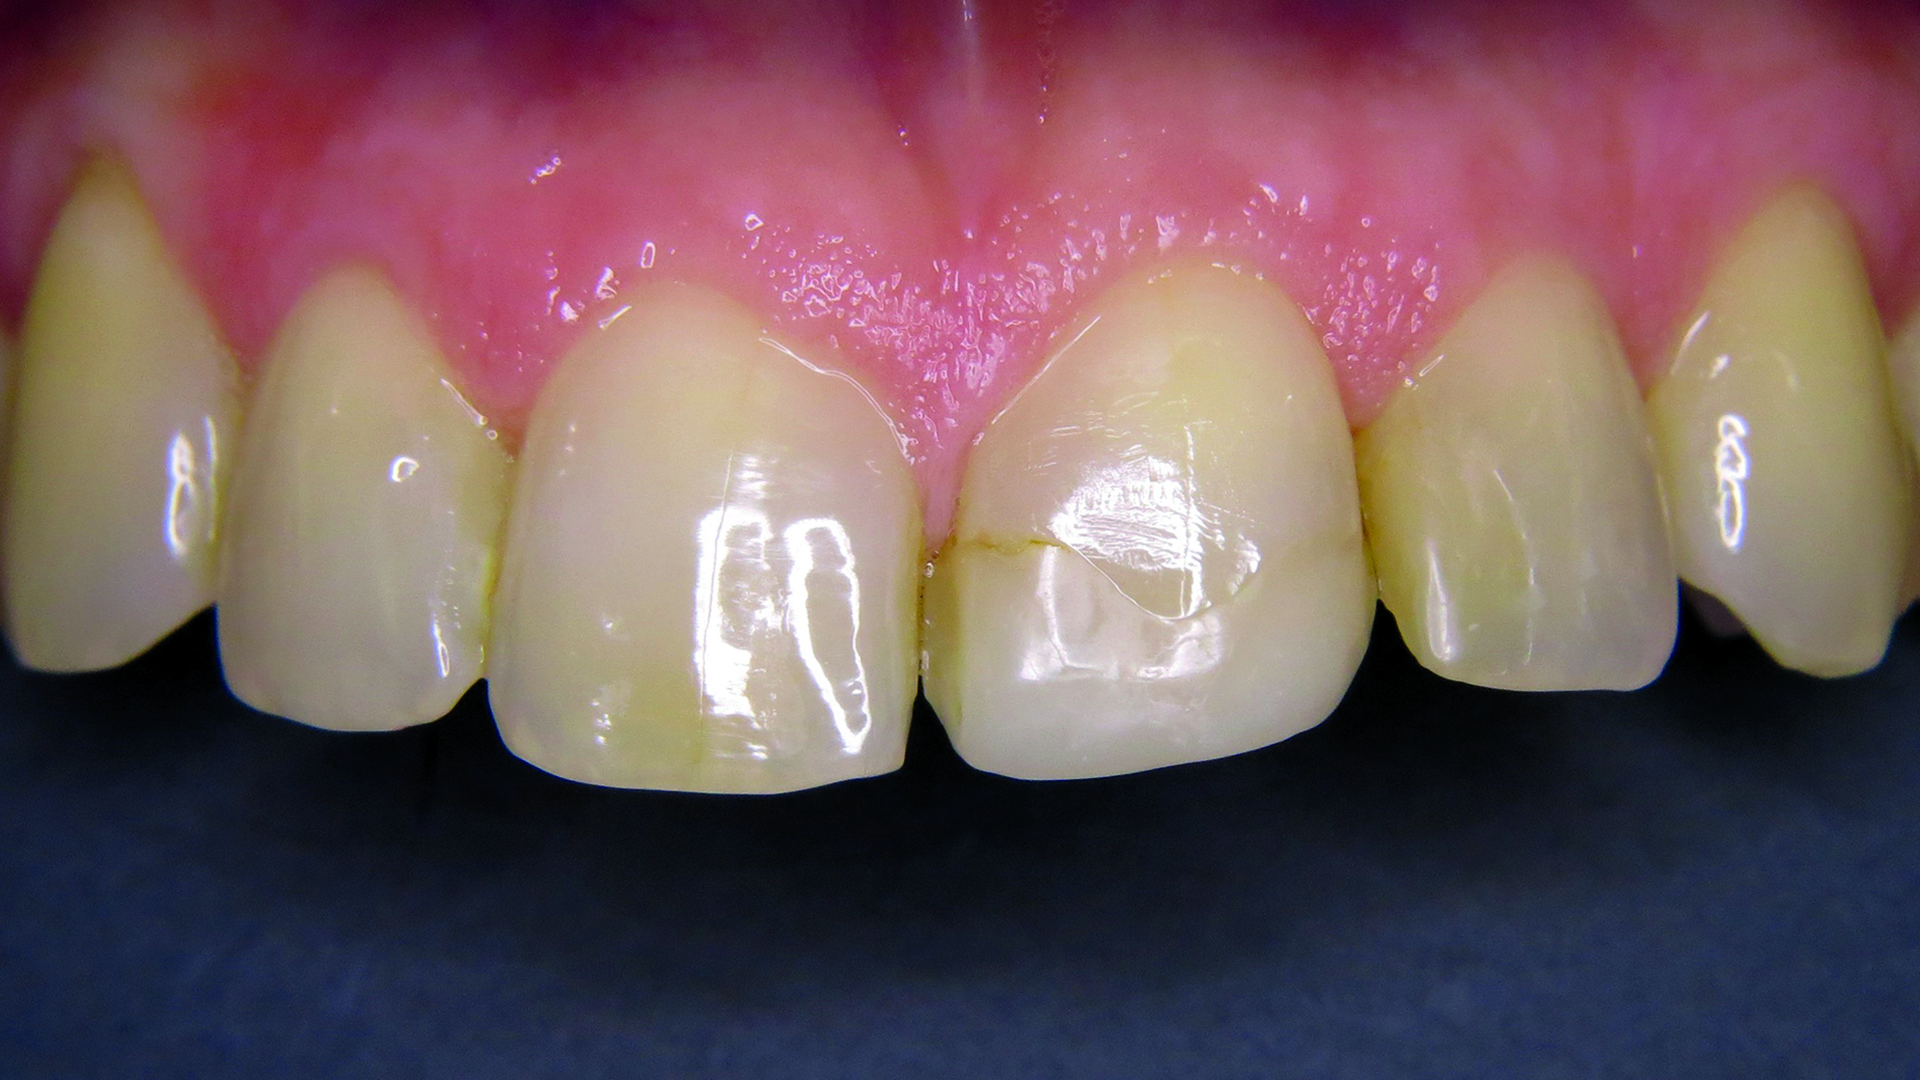

48-letnia pacjentka cierpiąca na alergię wywoływaną przez wiele czynników oraz z historią ataków padaczki w wywiadzie zgłosiła się z życzeniem szybkiego zaplanowania i wykonania estetycznej odbudowy zęba 21, leczonego 10 lat wcześniej (ryc. 1). Zaproponowano pacjentce wykonane analogowo lub cyfrowo uzupełnienie protetyczne lub odbudowę z wykorzystaniem kompozytu opartego na technologii ORMOCER®. Uwzględniając choroby towarzyszące, zdecydowano się zastosować izolację względną. Właściwym dla pacjentki rozwiązaniem okazała się bezpośrednia odbudowa zachowawcza z wykorzystaniem Admira Fusion 5 (VOCO GmbH, Niemcy), gdyż preparat ten nie zawiera klasycznych monomerów. Oczekiwania pacjentki dotyczące estetycznej odbudowy w jak najkrótszym czasie mogły zostać spełnione dzięki wzmocnionemu efektowi kameleona.

Ryc. 1. Pierwotna sytuacja kliniczna – wadliwa rekonstrukcja.

W aspekcie klinicznym stwierdzono w zębie 21 wadliwe wypełnienie z przebarwieniem brzegów i szczeliną brzeżną. Ząb charakteryzował się I stopniem ruchomości, nie był wrażliwy na opukiwanie i nie wykazywał zmian w przyzębiu.